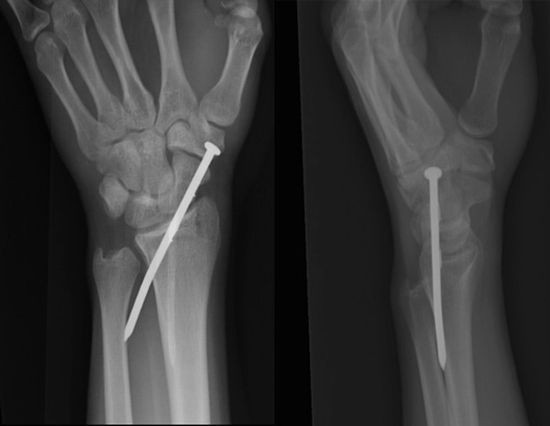

Radiografii terifiante: foarfece in cap, cuie in gat si furculite in mana

Surublenite infite in cap, plamani "dotati" cu cuie sau laringe "presarat" cu foarfece. Sunt numai cateva dintre cele mai ingrozitoare radiografii cu care s-au confruntat medicii de-a lungul timpului.

Iata mai jos o serie cu unele dintre cele mai "spectaculoase" radiografii.